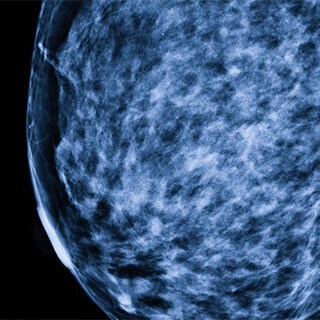

Mammograms detect fewer tumors among cancer survivorsWhile mammography reduces the risk of breast cancer among healthy women, scientists have found it does not detect as many new malignancies among women with a history of the disease.

Pooling data from several United States cancer registries, researchers measured the number of cancers detected among women within a year of a first screening. They found that women previously diagnosed with breast cancer had almost three times as many tumors discovered. However, the sensitivity of the mammograms in identifying growths in these patients was about 65% compared with 76% in women without cancer.

Another assumption is that x-ray based mammograms tend to pick up more ductal carcinoma in situ (DCIS), or localized tumors, than invasive cancers. The tests simply are better at finding calcifications associated with DCIS than the more deeply-embedded invasive tumors. Also, breast cancer survivors are more likely to develop metastases, which are more invasive, which could also explain the screen’s weaker sensitivity among previous patients. Still, she says, breast cancer patients should continue to get regular mammograms, along with even closer evaluation of their breast tissue.